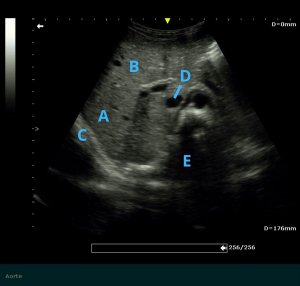

Image Echo L2 ch5_REV